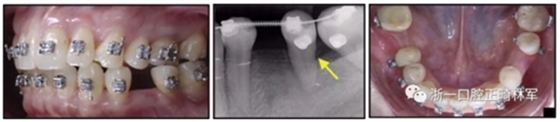

36歲;女性;尋求下頜左后方區(qū)域間隙管理的建議(圖1和圖2),通過(guò)治療獲得了良好的牙頜面效果(圖3和圖4)。她被診斷患有骨性I類和代償性牙性II類錯(cuò)合畸形,并且上頜左側(cè)尖牙缺失(圖1和2)。大約七年前,由于不可修復(fù)的齲齒,拔除了下頜左側(cè)第一和第二磨牙(圖5)。37相鄰的第三磨牙向近中移動(dòng)并傾斜入間隙,導(dǎo)致無(wú)牙頜間隙減小至約14 mm(圖2和圖5)。臨床和影像學(xué)評(píng)估顯示多發(fā)性齲損和在下頜右側(cè)567處有一不良的固定橋修復(fù)體(圖1和5)。此外,下頜左中切牙缺失,造成下頜中線向左側(cè)偏移約3 mm(圖1和圖2)?;颊咦栽V,她的右上第一前磨牙和左上尖牙在13歲時(shí)由其家庭牙醫(yī)拔除,因?yàn)樗鼈儽蛔枞筋a側(cè)萌出(圖1)。上頜第二磨牙缺失(未知病因),并且相鄰的第三磨牙已經(jīng)轉(zhuǎn)移到第二磨牙間隙中。如補(bǔ)充材料所示,美國(guó)正畸學(xué)差異指數(shù)DI是28分。種植體部位(下頜左側(cè)和右側(cè)第一磨牙)由于復(fù)雜性得到額外4分(補(bǔ)充材料)。

圖1. 治療前面部和口內(nèi)照片

圖5. 治療前的側(cè)位片(上圖)和全景(下圖)的X光片